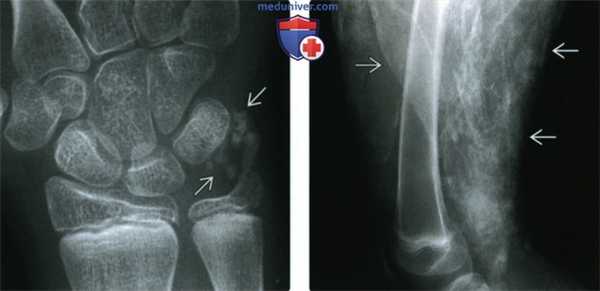

(Слева) Рентгенография в ПЗ проекции: в мягких тканях запястья визуализируются шаровидные кальцификаты. Также отмечаются шаровидные кальцификаты по ходу ладонной поверхности первого пальца (не представлены), оба этих признака указывают на ПСС.

(Справа) Рентгенография в боковой проекции, этот же пациент: определяются листовидные кальцификаты, в большей степени являющиеся признаком дерматомиозита. Хотя обе эти картины могут наблюдаться и при ПСС, и при дерматомиозите, их сочетание заставляет задуматься о наличии смешанного поражения соединительной ткани (синдром наложения).

(Справа) Рентгенография в ЗП проекции: в области запястья определяется кальцификация подкожно-жировой клетчатки и ТХВК. В 1-м ПЗП суставе определяется резорбция в области сустава и выраженный подвывих. Такая картина считается отличительным признаком ПСС.